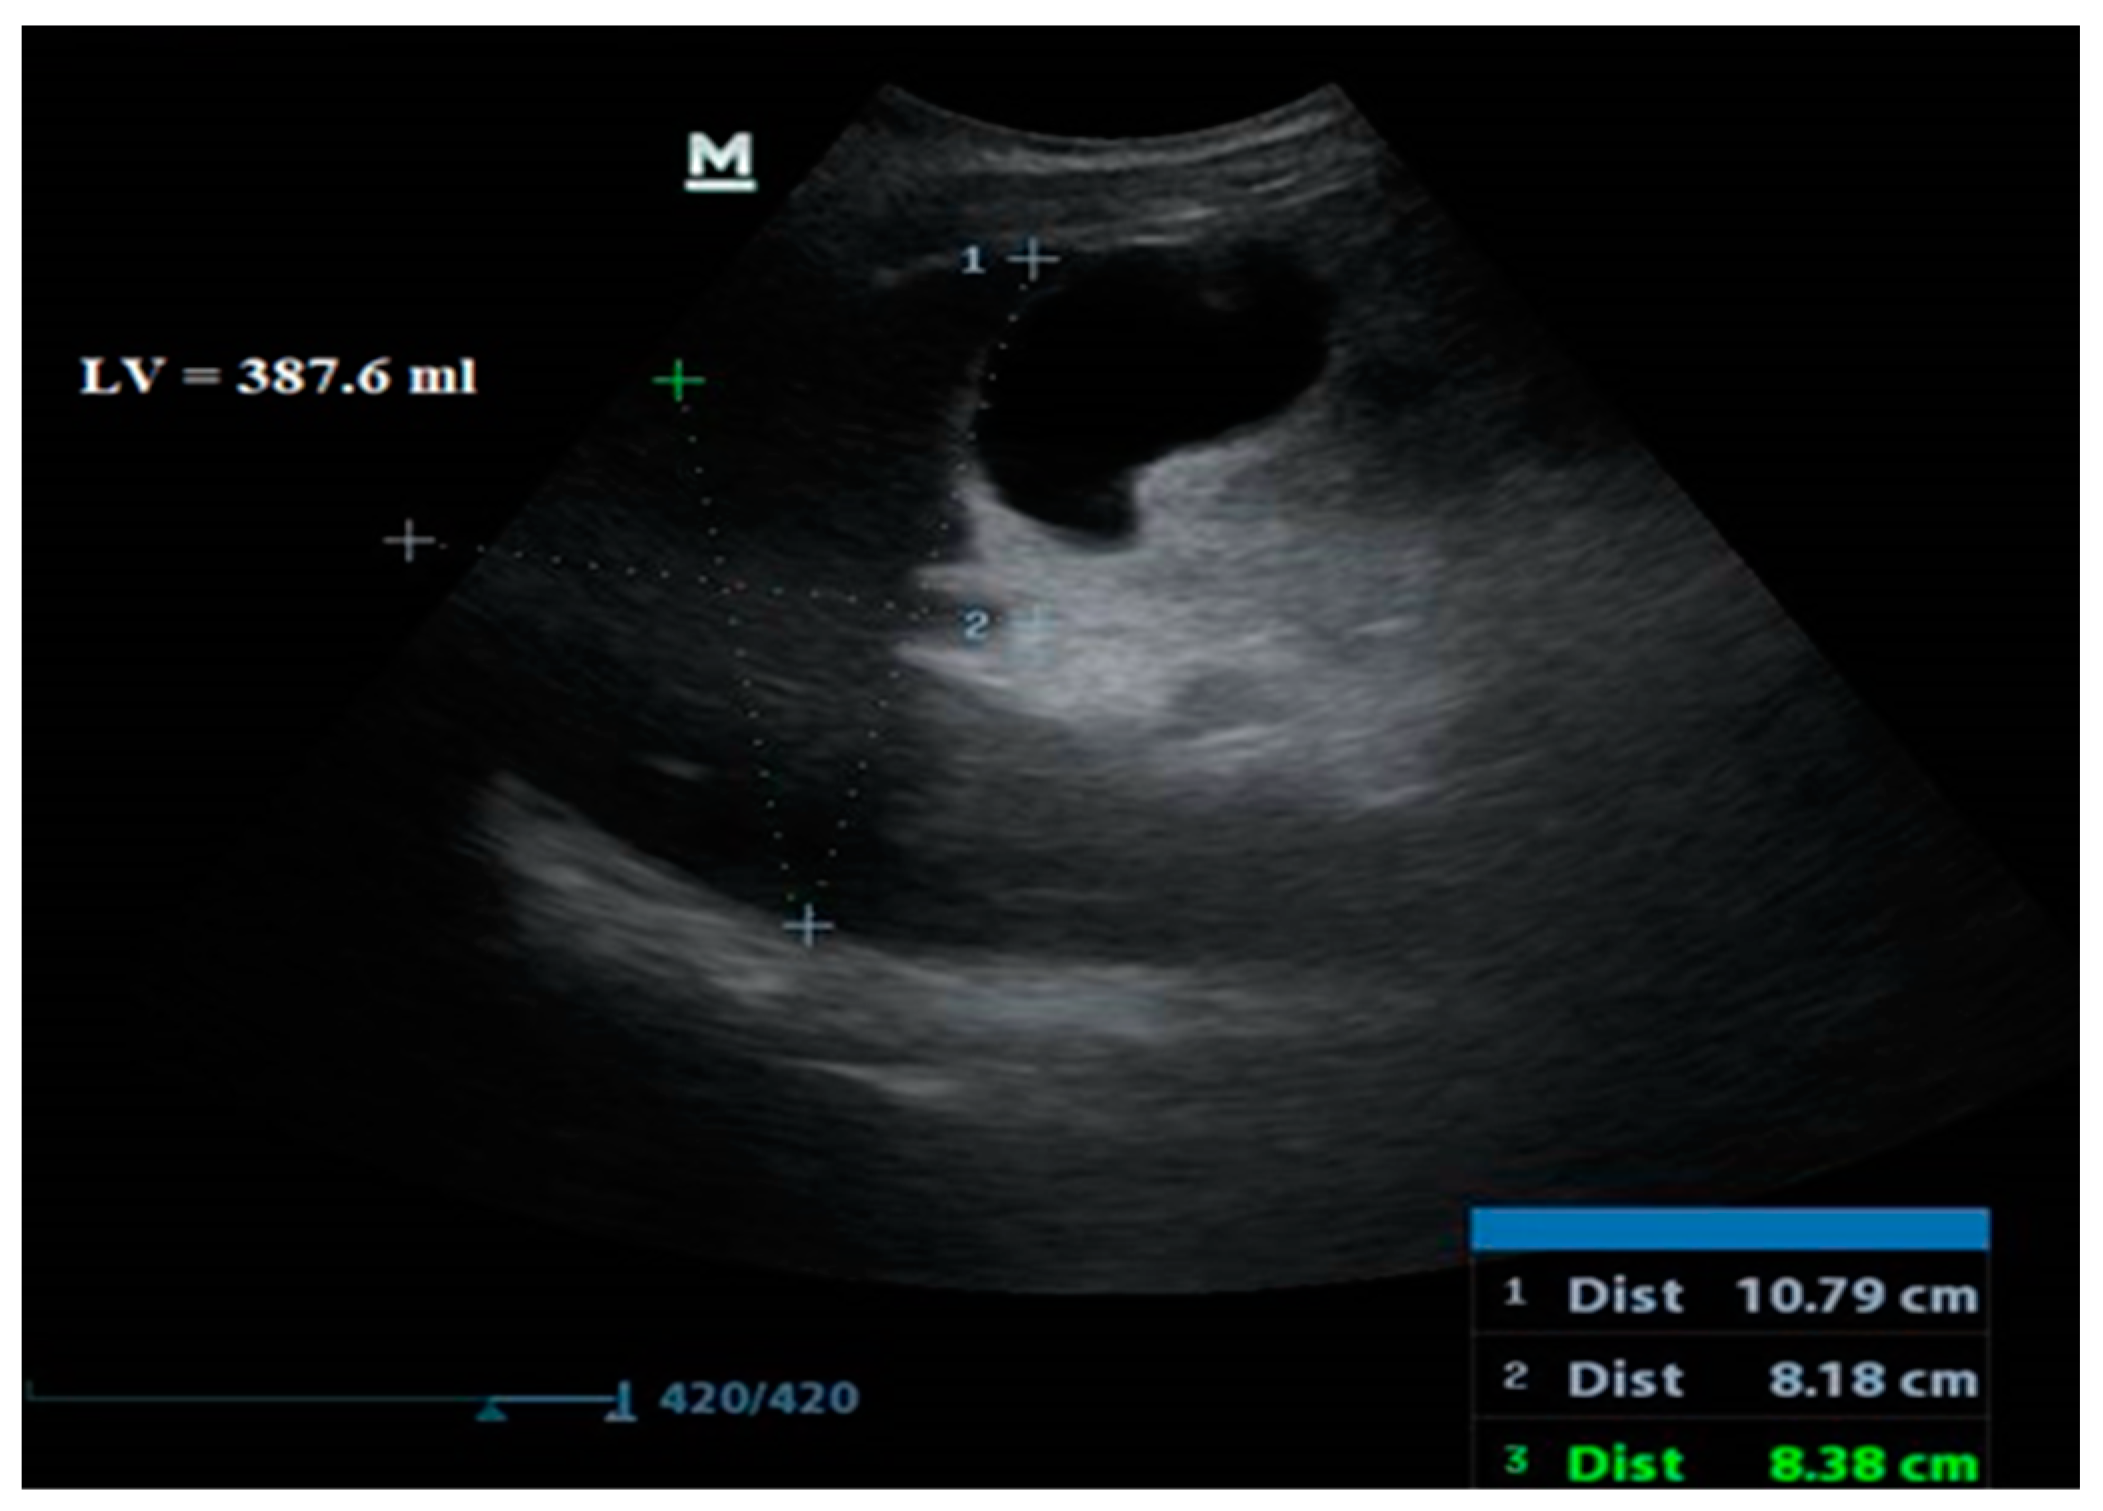

2.1.6. Abdominal Ultrasound Evaluation

| Liver Volume (mL) | 808.3 ± 147.8 | 593.5 ± 122.0 | 726 (403–1280) IQR 211 | 0.01 | <0.001 | |

| Liver Volume | −0.640 | 0.000 |

| Liver Volume | ≤682.3 | 95.24 76.2–99.9 | 85.71 72.8–94.1 | 74.1 58.8–85.1 | 97.7 86.1–99.7 | 0.935 0.849–0.980 | 0.81 | <0.001 |